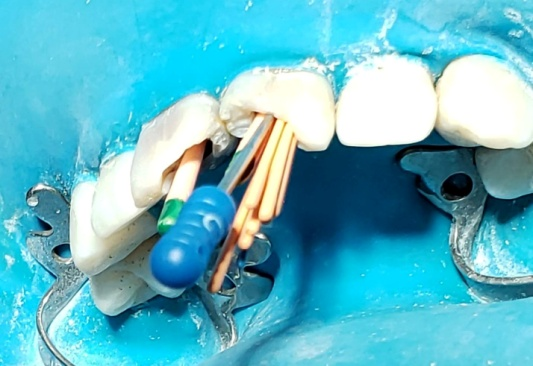

Una vez retirados los tornillos, se irrigó con hipoclorito de sodio al 2.5%, observándose salida de detritos oscuros y olor fétido. Luego, se empleó una lima K #10 25mm (Dentsply-Maillefer) (Fig. 8) como instrumento de exploración y pasaje. Esta lima permite determinar la permeabilidad, establecer la longitud de trabajo inicial y detectar posibles obstáculos o irregularidades en el trayecto del conducto (Cunha et al., 2020). Su uso es indispensable para preparar el camino para la instrumentación sin generar bloqueos ni desvíos. Se realiza la conductometría con limas K 25 de 25mm de largo Dentsply-Maillefer (Fig 9-10).

Conometría y verificación de la longitud de trabajo

Una vez finalizada la instrumentación escalonada, se procedió a realizar la conometría (Fig 14-15) utilizando conos taper 06 calibre 35 (Meta-Biomed), con las que se había logrado una leve resistencia en los tercios medio y apical. Esta elección permitió confirmar la longitud de trabajo de manera efectiva y predecir la adaptación de los conos de obturación. Se obtuvo una radiografía periapical de control con las limas posicionadas en los conductos (fig 10), la cual confirmó la coincidencia con la longitud previamente estimada (23 mm). También se registró la fotografía clínica correspondiente, evidenciando la locali- zación precisa de los conos dentro de los conductos (Fig. 9)

Fig. 9 Foto conductometría limas K 25

Fig. 10 Rx Conductometría